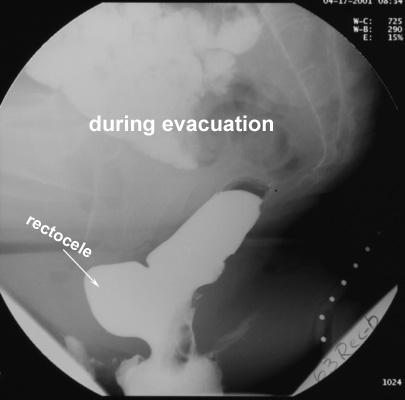

- During evacuation, part of the contrast material may be

sequestered in this pseudodiverticulum, and full rectal emptying may

not be achieved at the first attempt.

- Asymptomatic rectoceles are generally small (<2 cm in depth)

and rarely retain barium.

- Rectoceles in symptomatic patients generally are moderate

in size (2-4 cm) or large (>4 cm) and retain barium after

evacuation.